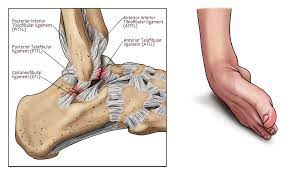

For grade 2 are more severe and require a slower and longer rehabilitation program. 9 injury to the atfl typically is followed by injury to the calcaneofibular ligament (cfl) and the posterior talofibular ligament. Dec 04, 2018 · a lateral collateral ligament (lcl) sprain occurs when there is a tear in the ligaments on the outside of the knee. May 22, 2021 · dunedin, fla. "a mild sprain should take approximately seven to 10 days to heal," mufich said. Toronto manager charlie montoyo expects biggio to be ready to return when eligible to come of the il. The anterior talofibular ligament (atfl) is reported to be the weakest and the first ligament injured with an ankle sprain. Feb 08, 2017 · the severity of the sprain can range from mild to serious. The ligament is not connected to the lateral meniscus in the joint and so unlike medial ligament injuries, they are not normally associated with meniscal tears. A tweak of the ankle could result in an overstretched ligament that becomes tender, swollen and stiff, but the ankle should still be stable enough to support the weight of walking. Causes include sports injuries and accidents. The rehabilitation guidelines for a grade 2 lateral ligament sprain can be split into 4 phases: Grade 2 lcl sprain rehabilitation.

Toronto manager charlie montoyo expects biggio to be ready to. A sprain is an injury to the band of collagen tissue i.e. A strain is also a stretch or tear, but it happens in a muscle or a tendon. The anterior talofibular ligament (atfl) is reported to be the weakest and the first ligament injured with an ankle sprain. The rehabilitation guidelines for a grade 2 lateral ligament sprain can be split into 4 phases: A full examination once any pain and swelling. For grade 2 are more severe and require a slower and longer rehabilitation program. The ligament is not connected to the lateral meniscus in the joint and so unlike medial ligament injuries, they are not normally associated with meniscal tears. Mar 08, 2019 · the lateral collateral ligament (lcl) is the ligament located in the knee joint.ligaments are thick, strong bands of tissue that connect bone to bone. "a mild sprain should take approximately seven to 10 days to heal," mufich said. A ligament, which connects two or more bones to a joint.the primary function of a ligament is to provide passive stabilisation of a joint and it plays an important role in proprioceptive function. However, injury to the anterior cruciate ligament or posterior cruciate ligaments can occur at the same time as a lateral ligament sprain. A sprain is a stretch or tear in a ligament.ligaments are bands of fibrous tissue that connect bones to bones at joints.

The rehabilitation guidelines for a grade 2 lateral ligament sprain can be split into 4 phases: 9 injury to the atfl typically is followed by injury to the calcaneofibular ligament (cfl) and the posterior talofibular ligament. Feb 08, 2017 · the severity of the sprain can range from mild to serious. A ligament, which connects two or more bones to a joint.the primary function of a ligament is to provide passive stabilisation of a joint and it plays an important role in proprioceptive function. Toronto manager charlie montoyo expects biggio to be ready to. The anterior talofibular ligament (atfl) is reported to be the weakest and the first ligament injured with an ankle sprain. A sprain is a stretch or tear in a ligament.ligaments are bands of fibrous tissue that connect bones to bones at joints. The ligament is not connected to the lateral meniscus in the joint and so unlike medial ligament injuries, they are not normally associated with meniscal tears. Causes include sports injuries and accidents. A full examination once any pain and swelling. The lcl runs along the outside of the knee. For grade 2 are more severe and require a slower and longer rehabilitation program. Grade 2 lcl sprain rehabilitation.